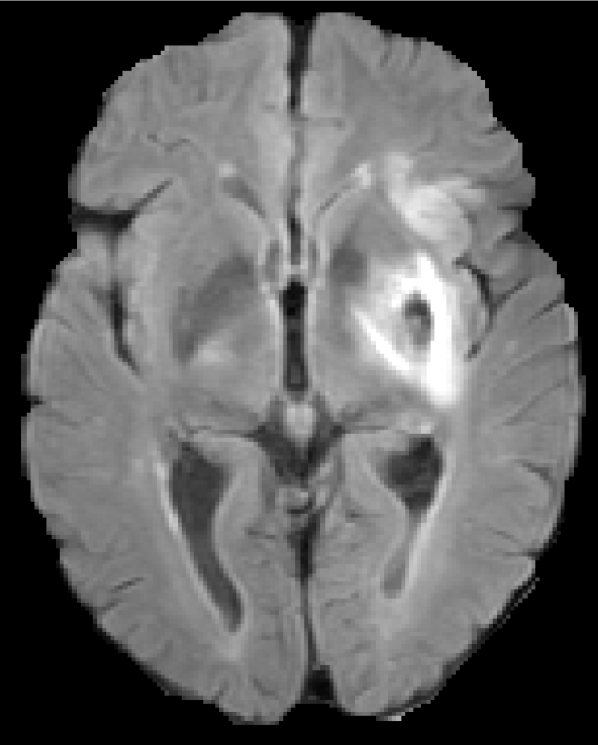

The given images are first pre-processed with a symmetric modality augmentation to allow learning of features based on the symmetry of brain hemispheres despite the small receptive field of the used patches. Explicit symmetry information was already shown to improve results for chronic stroke lesion segmentation [19]. In our case, instead of using one patch per hemisphere in a multi-path network we use a single joint patch with a single-path network. In practice, we augment the provided modality images with symmetric versions that swap the left and right hemispheres. We first flip one of the images along the mid-sagittal axis and then we apply FSL FLIRT [20] to perform a linear registration between the original and flipped image. Finally, the rest of modalities are registered using the same transformation. Figure 1 shows an example of the resulting symmetrically augmented modalities. These are then appended to the provided ones, effectively doubling the number of images for each patient. In this way, a single extracted patch will also include intensity information from the opposite hemisphere.

Figure 1: Provided and symmetrically augmented modalities from case 2 of the SISS training images.